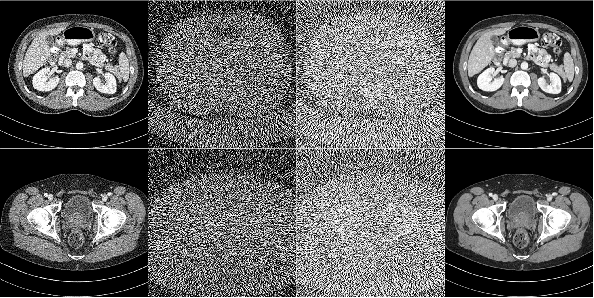

Noise and artifacts are intrinsic to low dose CT (LDCT) data acquisition, and will significantly affect the imaging performance. Perfect noise removal and image restoration is intractable in the context of LDCT due to the statistical and technical uncertainties. In this paper, we apply the generative adversarial network (GAN) framework with a visual attention mechanism to deal with this problem in a data-driven/machine learning fashion. Our main idea is to inject visual attention knowledge into the learning process of GAN to provide a powerful prior of the noise distribution. By doing this, both the generator and discriminator networks are empowered with visual attention information so they will not only pay special attention to noisy regions and surrounding structures but also explicitly assess the local consistency of the recovered regions. Our experiments qualitatively and quantitatively demonstrate the effectiveness of the proposed method with clinic CT images.